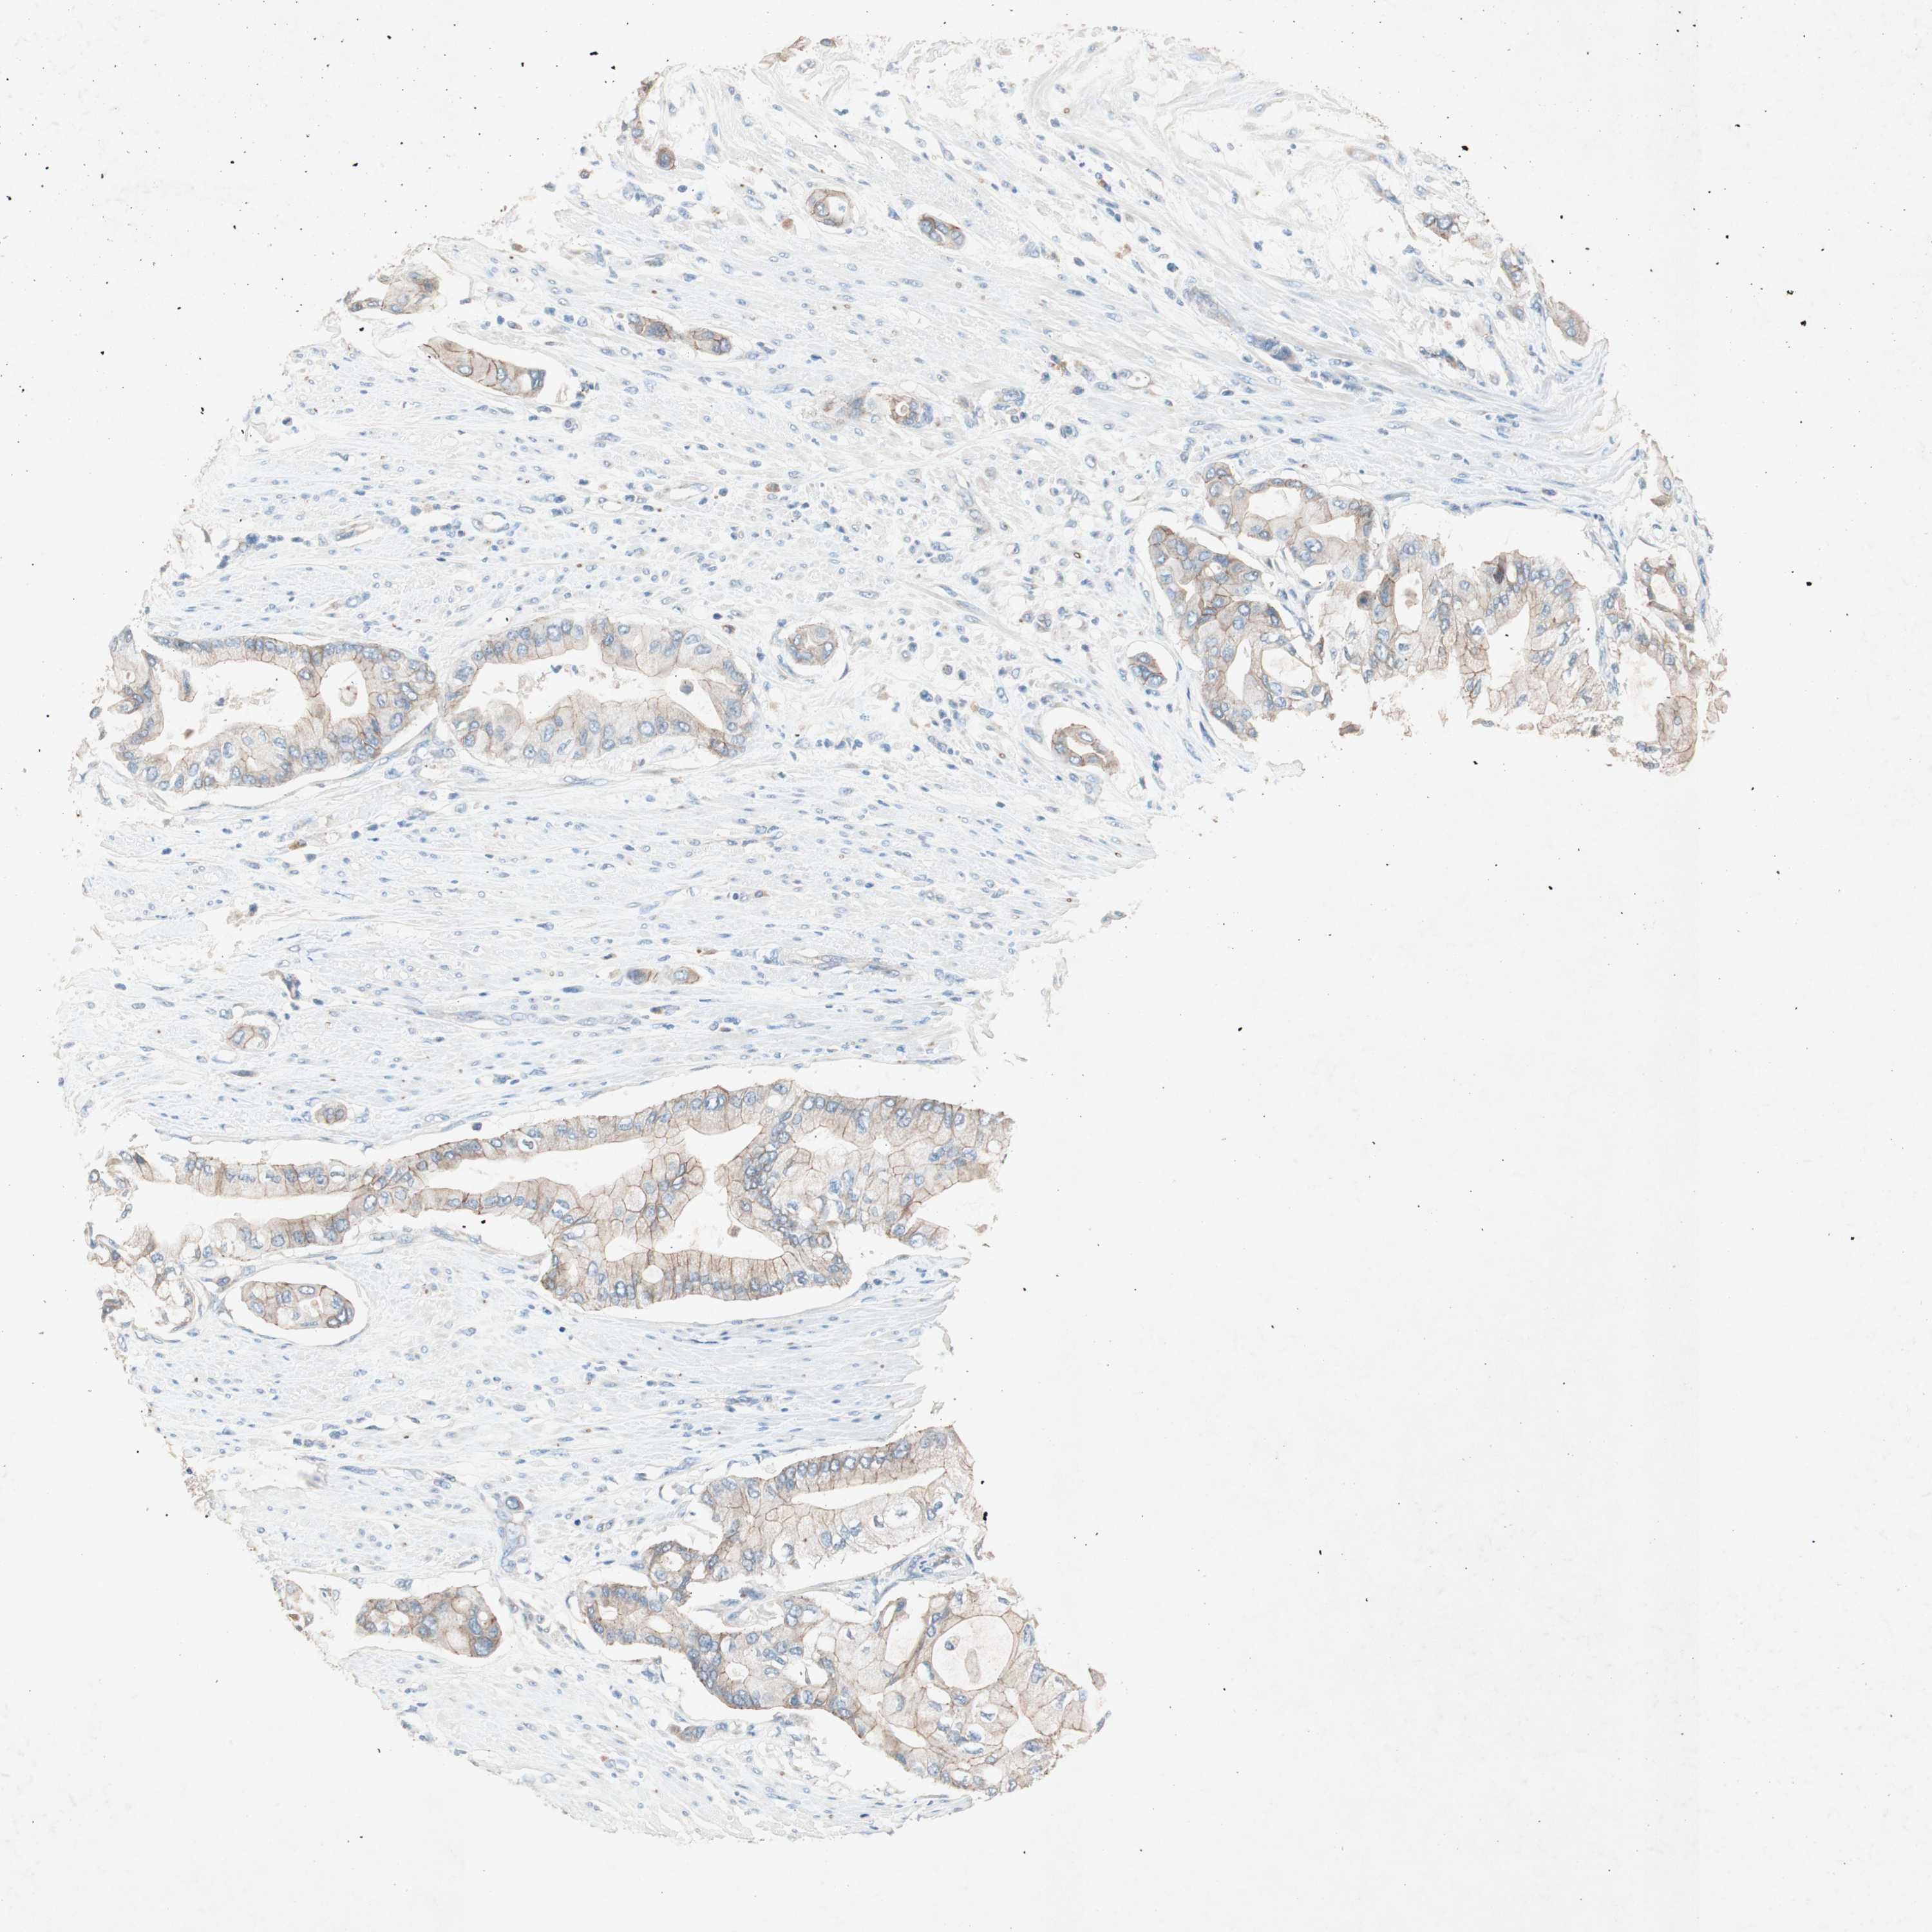

PANCREATIC CANCER - Protein expressioni

A mouse-over function shows sample information and annotation data. Click on an image to view it in a full screen mode. Samples can be filtered based on level of antibody staining by selecting one or several of the following categories: high, medium, low and not detected. The assay and annotation is described here.

Note that samples used for immunohistochemistry by the Human Protein Atlas do not correspond to samples in the TCGA dataset.

Antibody stainingi

Antibody staining in the annotated cell types in the current human tissue is reported as not detected, low, medium, or high, based on conventional immunohistochemistry profiling in selected tissues. This score is based on the combination of the staining intensity and fraction of stained cells.

Each image is clickable and will lead to virtual microscopy that enables deeper exploration of all samples and also displays staining intensity scores, fraction scores and subcellular localization as well as patient and tissue information for each sample.

Antibody HPA006873

Staining

High

Medium

Low

Not detected

Intensity

Strong

Moderate

Weak

Negative

Quantity

>75%

75%-25%

<25%

None

Location

Nuclear

Cytoplasmic/membranous

Cytoplasmic/membranous,nuclear

Adenocarcinoma, NOS

Adenocarcinoma, metastatic, NOS